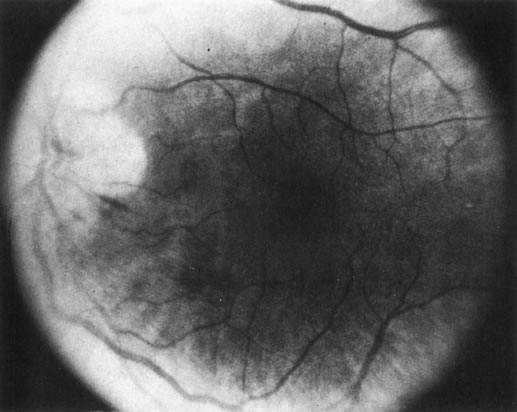

Unfortunately, imaging studies are not always diagnostic. The A- and B-scans shown in Figures 3 and 4 were from a patient with unilateral media opacity referred for evaluation and treatment of a presumed uveal melanoma. Occasionally, if the cataractous lens is scanned tangentially, artifact can occur. A repeat ultrasound at our institution was negative for tumor, and the referral ophthalmologist who performed a cataract extraction noted that no tumor was present and that the patient has an excellent visual outcome. In contrast, the patient shown in Figure 5 was referred with a presumed uveal melanoma with secondary inflammation and a history similar to that described for the patient shown in Figure 111 Ultrasound and CT examinations were not diagnostic. Because the eye was blind and painful, it was enucleated, and an extremely necrotic uveal melanoma was noted histologically. In some necrotic melanomas, the fundus cannot be visualized and the diagnosis cannot be established with imaging studies. Very rarely, a necrotic uveal melanoma can produce sufficient pigment dispersion into the vitreous to obscure the correct diagnosis.12